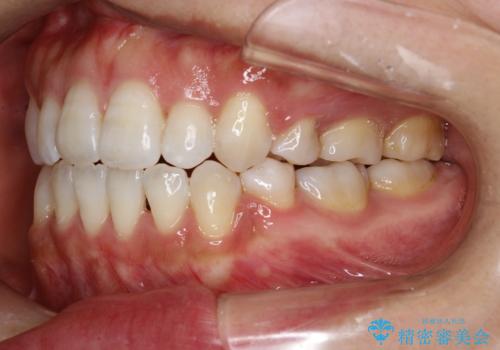

- 前歯がガタガタなのと、前歯でものが噛めないことを主訴に来院されました。

前歯の叢生があり、上下の前歯が接触していない開咬という状態でした。

左側の上下の前から4番目の歯を抜歯して、矯正することとしました。